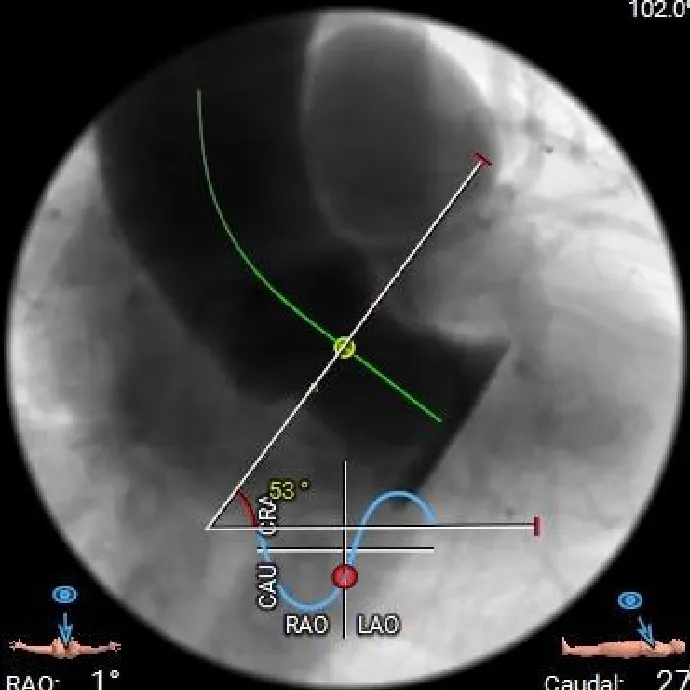

CASE Ⅲ

患者基本情况

基础信息:76岁,男性。

术前CT分析

主动脉根部测量

Annulus

25mm

LVOT

25.6mm

SOV

35.3*36.8*38.2mm

STJ

37mm

AAO

41.4mm

心脏角度

53°

-

纯反流三叶瓣,瓣环内径25mm

流出道直筒型

瓣叶无明显增厚、无钙化

升主动脉扩张

手术策略制定

麻醉方式:全身麻醉;

冠脉风险:低;

球囊扩张策略:不预扩;

瓣膜型号:ScienCrown TAVTF29mm(oversize 16%);

入路选择:右侧股动脉主入路,超硬导丝支撑下植入大鞘;

手术操作:该患者流出道直筒型,瓣上锚定空间有限,需充分利用瓣环及瓣下空间参与锚定,瓣膜需瓣下释放,术中通过顶导丝等操作保证瓣膜同轴性,当瓣膜完全展开后,多角度评估其稳定性。

术中影像

初始造影确定无冠窦

瓣膜瓣下定位释放,全展开后位置良好

左侧位造影,瓣膜位置可,选择脱钩

脱钩后造影,瓣膜位置可,无反流